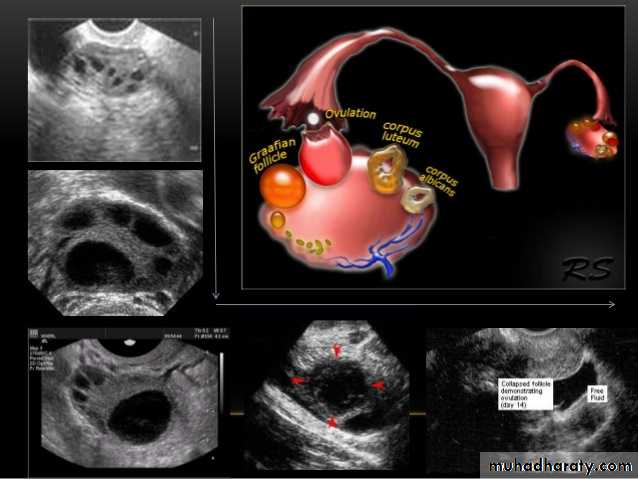

Ovarian cysts

Ovarian cysts are commonly encountered in gynecological imaging, and vary widely in etiology, from physiologic, to complex benign, to neoplastic.

Small cystic ovarian structures should be considered normal ovarian follicles unless the patient is pre-pubertal, post-menopausal, pregnant, or the mean diameter is >3.0 cm

Radiographic features

Ultrasound is usually the first imaging modality for assessment of ovarian lesions. Simple ovarian follicular cysts are:

anechoic

intraovarian or exophytic;

have an imperceptible wall